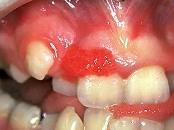

单项选择题组图是牙龈瘤患者,有关此病的描述不正确的是 ( )

A、生长较慢

B、肿块较局限

C、可能导致牙松动

D、为恶性病变

E、可破坏牙槽骨壁